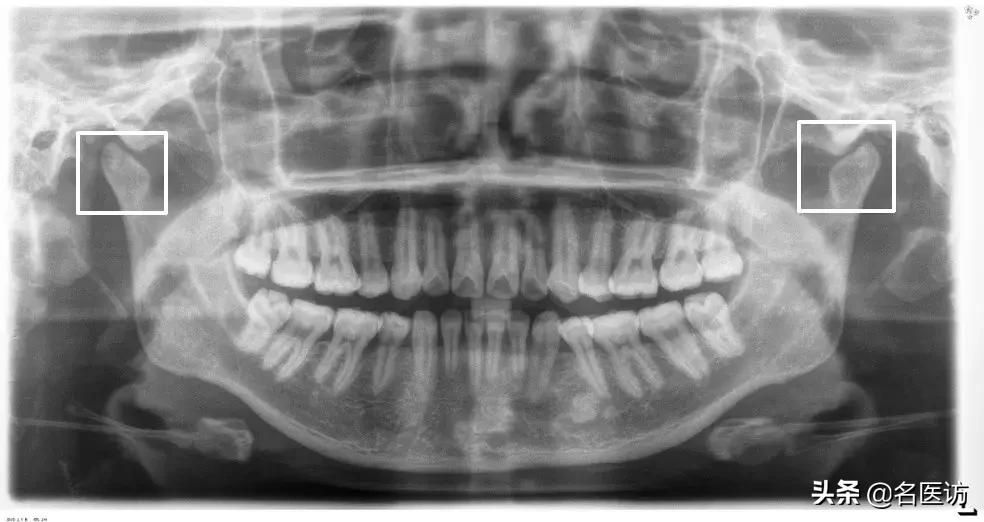

2、牙齿异常

阻生牙、埋伏牙和恒牙的先天缺失是错颌畸形的原因之一。阻生牙常压迫相邻牙齿并导致相邻牙齿牙根的吸收,而阻生的第三磨牙(俗称智齿)如果没有在矫正前拔除,很可能会成为日后牙齿问题复发的罪魁祸首。

埋伏牙

多生牙

阻生牙